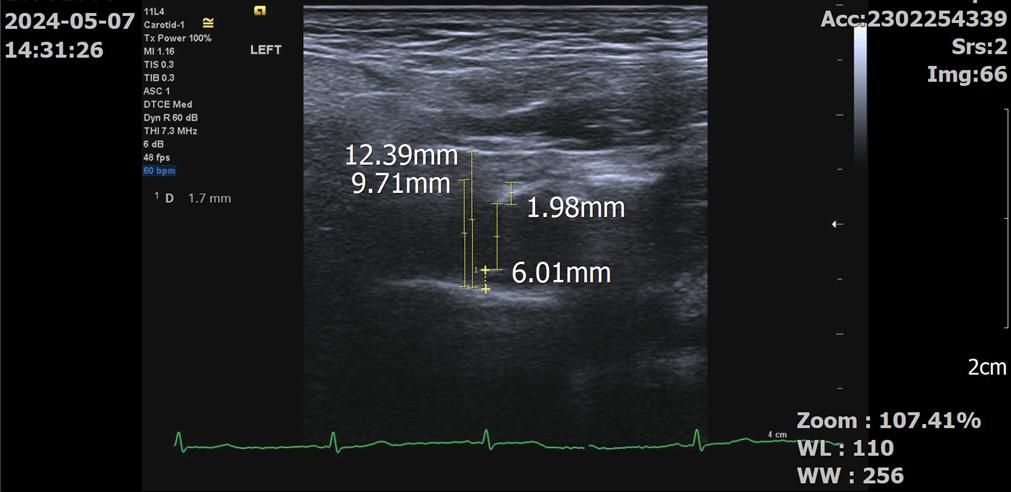

좌측 총경동맥입니다.

병원에서 재주신 플라크 사이즈는

CCA: 2.9 입니다.

위 영상 캡처본 기준으로 경동맥 협착률은 얼마정도라고 보아야 할지요?